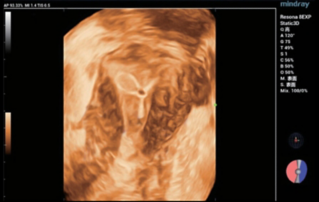

?? ?? ??? ?????(Endocavity volume convex array transducer)(DE10-3WU, Resona 7, ?????)? ??? ??? ???, ??? ?? 1/3 ?? ? ??(anterior vaginal wall)? ???? 18x14 mm ??? ?? ??(an ovoid-shaped formation) with a parietal fine suspension, ????? ??? ???? ??(non-displaced), ????,? CDI ??? ?? ?? ???? ????????. 3D ??? -? ??? ? ??(hyperechoic septa)? ?? ???? ??? ?? ??.

?? ??? ?? ???(Volumetric reconstruction)? ??? ??? ?? ??? ?? ??? ??? ? ??? ?? ??????? ??? ??? ??? ???.